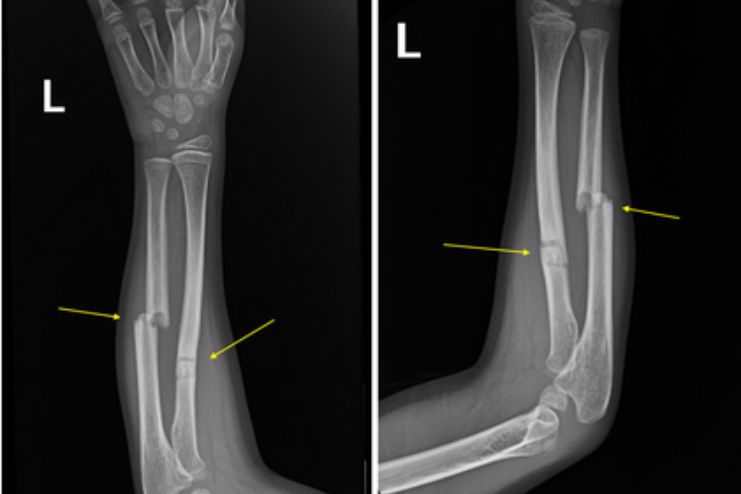

ఫ్రాక్చర్ Fracture

చేయి నొప్పి కూడా గుర్తించబడని ఫ్రాక్చర్ విరిగిన ఎముక యొక్క లక్షణం కావచ్చు. ఫ్రాక్చర్ను సూచించే లక్షణాలు:

- నొప్పి

- వైకల్యం

- వాపు

అనుమానిత ఫ్రాక్చర్కు వైద్య సలహా తీసుకోవడం ముఖ్యం. ఎముక సరిగ్గా నయం అయ్యేలా చూసుకోవడానికి వైద్య చికిత్స అవసరం.